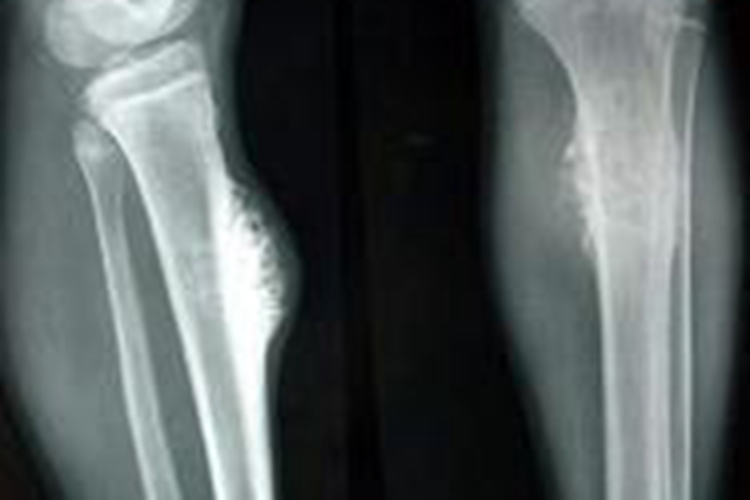

随着骨癌的发展,疼痛会持续加重,有刺痛或灼痛感,夜间或着凉后较明显,小腿皮肤呈酱紫色、皮紧发亮、小腿活动障碍,容易引起胫骨病理性骨折。